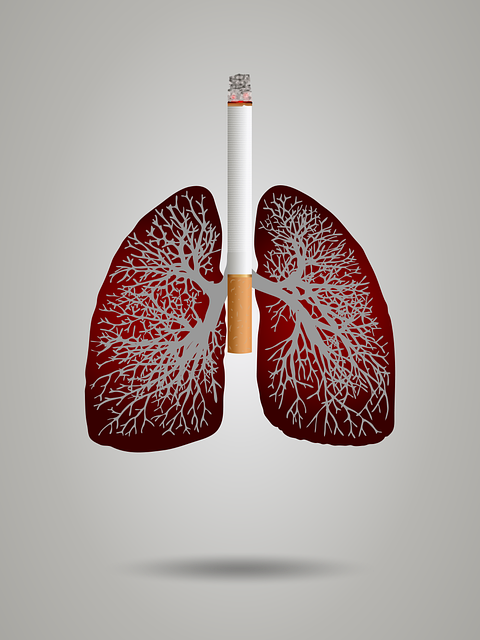

조기 발견이 생명을 바꿉니다

폐암은 초기 증상이 모호한 만큼 정기적인 검진이 가장 강력한 예방법입니다. 특히 40세 이상 흡연 경력이 있는 분들은 저선량 흉부 CT 검사를 통해 폐 건강을 체크하는 것이 매우 효과적입니다.